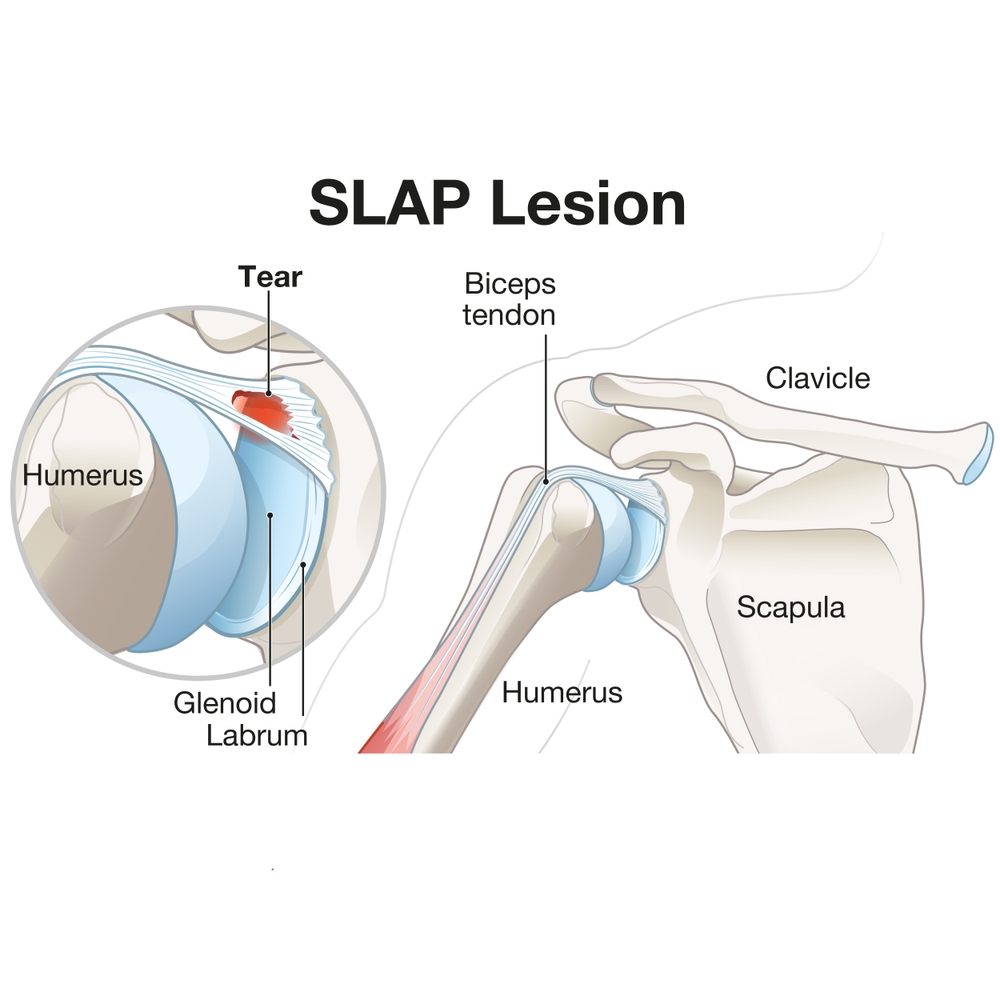

Rotator Cuff Pain: K Tape + Rehab Short-Term Effects

Nguyen, T. N. A., Nguyen, N. H., Vu, D. K., & Cu, L. T. N. (2025). Short-term effects ofKinesiotaping combined with a rehabilitation program for rotator cuff-related shoulder pain: Arandomized, ...

Rotator Cuff Pain: K Tape + Rehab Short-Term Effects

Nguyen, T. N. A., Nguyen, N. H., Vu, D. K., & Cu, L. T. N. (2025). Short-term effects ofKinesiotaping combined with a rehabilitation program for ...

肩痛:保守治疗的有效性

参考文献:Steuri, R.、Sattelmayer, M.、Elsig, S.、Kolly, C.、Tal, A.、Taeymans, J. 和 Hilfiker, R. (2017)。保守干预措施(包括运动、手法治疗)的有效性......

比较四种常见肩部手术的恢复率

快速审查:Case Peters 比较四种常见肩部手术的恢复率 Grubhofer, F., Martinez, ARM, Ernstbrunner, L., Haberli, J., Selig, ME, ...

肩胛本体感觉神经肌肉促进对粘连性肩关节囊炎患者疼痛和残疾的影响

由 Melissa Miller Mishra, N.、Mishra, A.、Charaniya, P. (2019) 审阅。肩胛本体感觉神经肌肉促进对粘连患者疼痛和残疾的影响